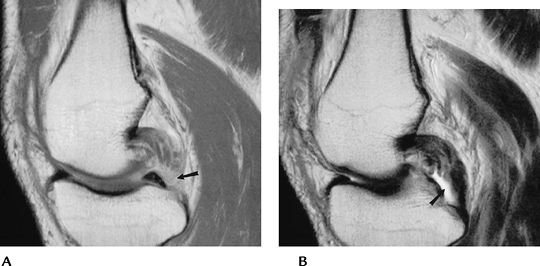

![]() |

FIGURE 5-74 Sagittal proton density (A) and T2-weighted (B) images demonstrate an ACL ganglion (arrow).